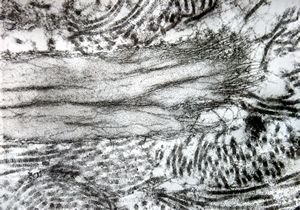

F,39y. | collagen and elastin - aorta

F,39y. | collagen, elastin and oxytalan microfibrils

F,45y. | collagen fibril - skin

F,29y. | collagen, elastin and oxytalan microfibrils - endomyocardial fibrosis